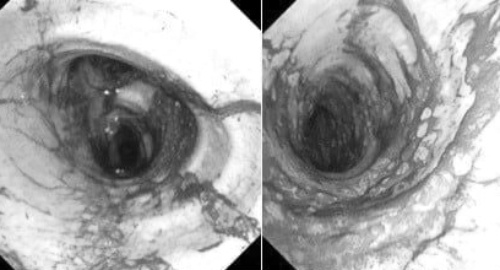

Đường thở của cả hai người bệnh bám nhiều bụi đen từ khói và tổn thương viêm sung huyết toàn bộ đường thở. Ảnh: BVCC.

Đáng chú ý, nhận định nguy cơ tổn thương đường thở nghiêm trọng và biến chứng lâu dài, các bác sĩ chuyên khoa hô hấp đã thực hiện nội soi phế quản ống mềm và rửa phế quản tại giường ngay trong ngày nhập viện, đồng thời lặp lại nhiều lần trong những ngày sau đó.

Kỹ thuật này giúp loại bỏ muội than, dịch tiết và các chất kích thích tích tụ trong đường thở, qua đó giảm viêm và cải thiện chức năng hô hấp cho người bệnh.